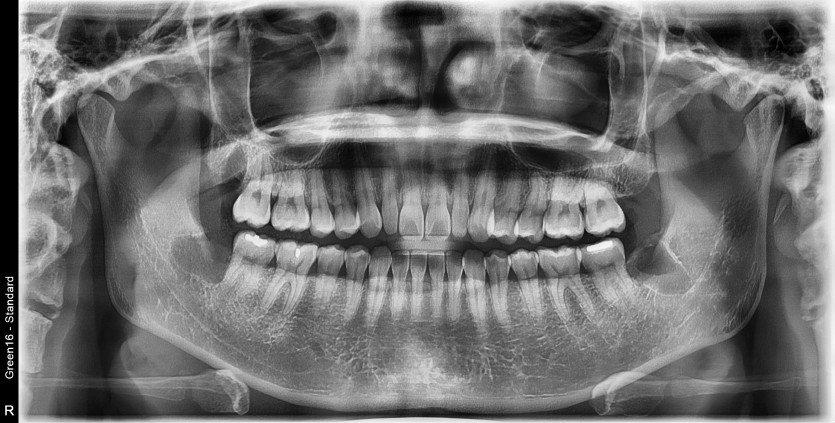

#18,38,48 사랑니 발치

구강 외과 전문의가 당일 발치했습니다.